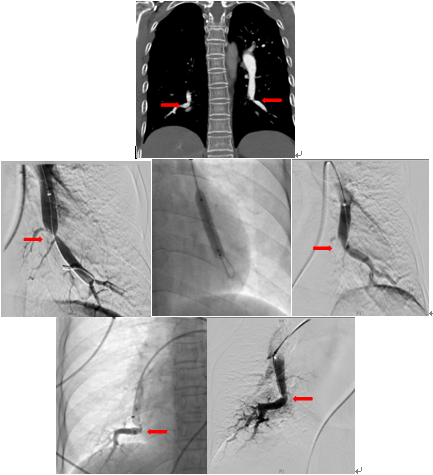

术前双侧肺动脉主干内血栓,术中溶栓后改善,术后复查主干血栓消失

北京清华长庚医院血管外科团队在吴巍巍主任的带领下联合麻醉科心内科呼吸科重症医学科等兄弟科室充分评估患者病情明确患者手术指征制定详细的围手术期治疗预案,与患者及家属充分沟通手术的必要性及相关风险后决定采用肺动脉球囊扩张成形术治疗。这是血管外科在静脉血栓栓塞性疾病治疗中的又一次大胆的尝试,无论是医生或是患者均承担了相当大的风险及压力。219日在麻醉科的严密监测下吴巍巍主任、赵俊来医通过右侧股静脉入路选择进入患者左肺动脉基底段狭窄部位,完成肺动脉球囊成形术,球囊扩张后肺动脉形态改善患者术后在监护病房观察一天后顺利返回普通病房,患者恢复顺利。于225再次行右侧肺动脉基底段球囊扩张。患者术后6分钟步行距离明显提高,术后2天即可行走450m,肺动脉力由术前82mmHg降至68mmHg患者顺利出院,由于双侧肺动脉病变广泛,此后还将密切随诊,择期再次行其余部位的肺动脉腔内治疗。

双侧肺动脉基地段狭窄球囊扩张前后对比